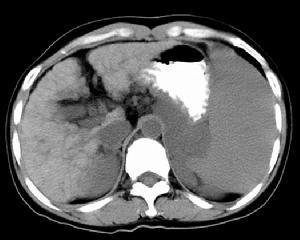

血吸蟲性肝病 CT表現7、肝血流圖反映門脈高壓,它和肝炎肝硬化不同點是高:張波比例較高。主要波形為低平波,分別占55%與45%,後者能是肝內門靜脈分支閉塞、動靜脈短路,肝供血減少表現為低波,手術後低平波轉變為高舒張波及正常波、高舒張波也轉變為常波。肝血流圖的各項指標,除舒張波波幅外,亦有明顯改變,要是平均波幅增高,舒張指數降低,表明脾切除後肝血液循環改善。

8、CT慢性和晚期血吸蟲病可有肝內鈣化,特別多見於肝右;葉,有地圖樣或線條狀改變。晚期更有肝萎縮,肝裂增寬,肝緣不光整、凹凸不平及結節狀突起,左右肝葉比例失調,肝脾密度的改變,亦可視脾腫大及腹水,但最具特徵性的是存線上條高密度影肝實質內有數量不等的線條狀高密度影,有呈弧線狀,有呈密集連線成格線狀或環狀,這與其病理特點幹線型肝硬化,沿門脈分支增生的纖維呈樹枝形分布有關。